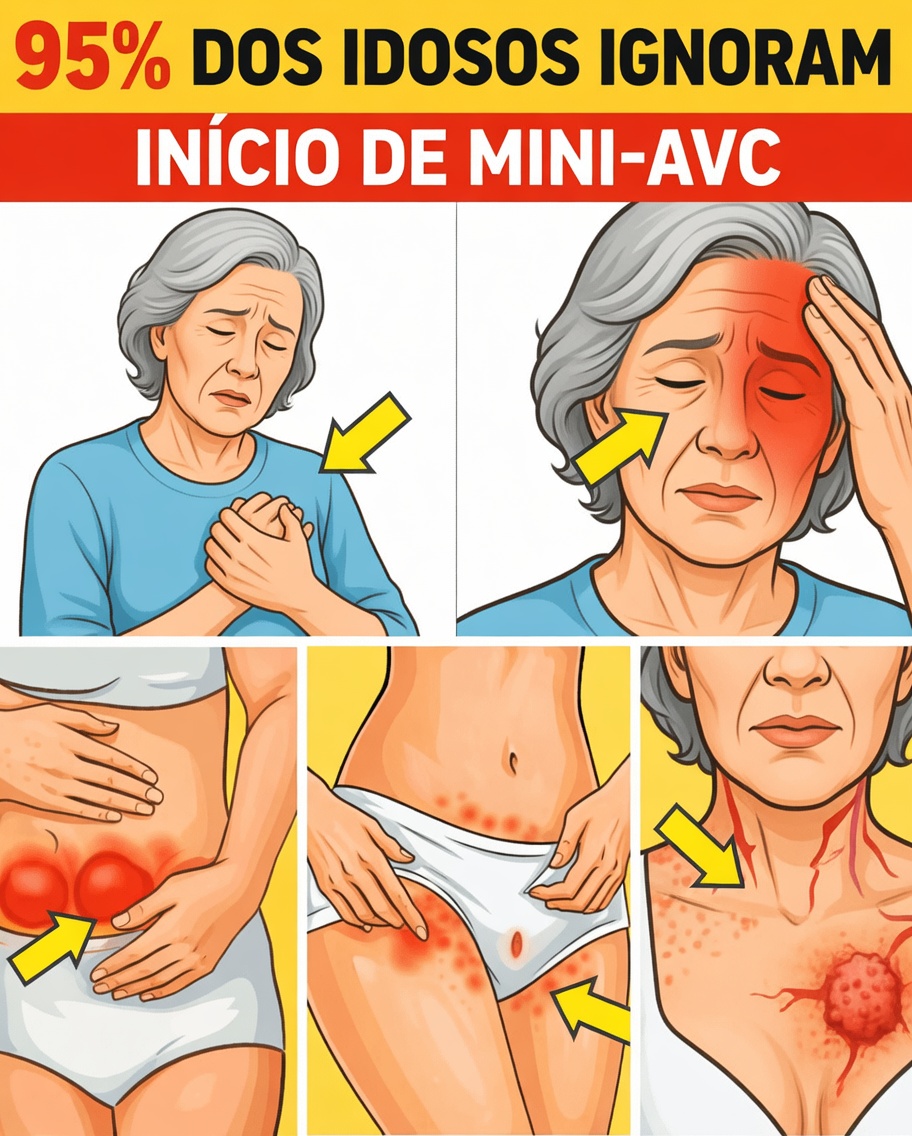

10 sintomas de mini AVC silencioso que quase ninguém nota depois dos 60

Em muitos casos, esses episódios aparentemente inofensivos podem ser sintomas de mini AVC silencioso, indicando um risco mais sério à frente se não forem avaliados. Eles se confundem facilmente com “coisas da idade”, alimentando o medo de que algo grave esteja se desenvolvendo sem ser percebido e possa roubar seu estilo de vida ativo.

A parte positiva é que, ao reconhecer cedo os sintomas de mini AVC silencioso, você ganha tempo para buscar ajuda médica adequada. A seguir, descubra os 10 sintomas de mini AVC silencioso mais ignorados, com destaque especial para o sinal surpreendente que quase todo mundo deixa passar, no item 4.

10 sintomas de mini AVC silencioso frequentemente ignorados

Abaixo estão os 10 sinais mais subestimados. Se você se reconhece em algum deles, especialmente se os episódios surgem de repente e passam rápido, vale conversar com seu médico.

5. Dormência ou formigamento que vai e vem em apenas um lado do corpo

Aparece de repente uma sensação de “agulhadas” ou dormência no rosto, braço ou perna de apenas um lado, que some em pouco tempo. Esse tipo de dormência unilateral é considerado um dos principais sintomas de mini AVC silencioso, especialmente em pessoas acima de 60 anos, de acordo com a American Stroke Association.

É muito comum explicar esses episódios como “má circulação”, “posição errada ao dormir” ou “membro que dormiu”. Porém, se o formigamento surge sem motivo claro, acomete sempre o mesmo lado e se repete, isso pode indicar um problema vascular cerebral transitório.

2. Queda momentânea de um lado do rosto ou sorriso torto

Ao falar ou sorrir diante do espelho, você percebe que um lado do rosto parece descer ou ficar mais “mole”, mas alguns minutos depois tudo volta ao normal. Essa fraqueza facial temporária é um dos sinais clássicos usados no teste FAST (Face, Arms, Speech, Time) para identificar AVC – e também pode aparecer em mini AVC silencioso.

Como o rosto volta rapidamente ao normal, muitas pessoas atribuem o episódio a cansaço ou a ter “dormido em posição estranha”. No entanto, uma assimetria súbita – um sorriso torto, pálpebra que cai, cantos da boca desiguais – indica possível comprometimento de áreas cerebrais que controlam os músculos da face.

Mesmos que dure pouco, esse é um dos sintomas de mini AVC silencioso que mais apontam para risco de um AVC completo no futuro. Por isso, vale registrar o horário, tirar uma foto se possível e relatar ao médico.

1. Fraqueza súbita em um braço, perna ou em todo um lado do corpo

O sintoma número 1, frequentemente ligado ao “AVC clássico”, também pode surgir de forma breve em um mini AVC silencioso: de repente, um braço ou uma perna perdem força, segurando objetos ou caminhando se torna difícil, e alguns minutos depois tudo melhora.

Essa fraqueza unilateral súbita é um dos sinais mais importantes de alerta. Pode ser algo como deixar cair uma xícara sem entender por quê, arrastar levemente um pé ao andar ou não conseguir levantar o braço como de costume.

Mesmo que a força volte, isso pode indicar que uma área do cérebro ficou temporariamente sem fluxo sanguíneo adequado. Ignorar esse tipo de sintoma de mini AVC silencioso é abrir espaço para um AVC mais grave ocorrer depois, muitas vezes sem aviso adicional.